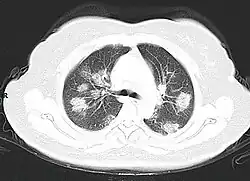

From the CT scans of COVID-19 infected lungs, white patches were observed containing fluid known as ground-glass opacity (GGO) or simply ground glass.[130] This tended to correlate with the clear jelly liquid found in lung autopsies of people who died of COVID-19. One possibility addressed in medical research is that hyuralonic acid (HA) could be the leading factor for this observation of the clear jelly liquid found in the lungs, in what could be hyuralonic storm, in conjunction with cytokine storm.[131]

Imaging

Chest CT scans may be helpful to diagnose COVID‑19 in individuals with a high clinical suspicion of infection but are not recommended for routine screening.[175][187] Bilateral multilobar ground-glass opacities with a peripheral, asymmetric, and posterior distribution are common in early infection.[175][188] Subpleural dominance, crazy paving (lobular septal thickening with variable alveolar filling), and consolidation may appear as the disease progresses.[175][189] Characteristic imaging features on chest radiographs and computed tomography (CT) of people who are symptomatic include asymmetric peripheral ground-glass opacities without pleural effusions.[190]

Many groups have created COVID‑19 datasets that include imagery such as the Italian Radiological Society which has compiled an international online database of imaging findings for confirmed cases.[191] Due to overlap with other infections such as adenovirus, imaging without confirmation by rRT-PCR is of limited specificity in identifying COVID‑19.[190] A large study in China compared chest CT results to PCR and demonstrated that though imaging is less specific for the infection, it is faster and more sensitive.[174]

By a variety of mechanisms, the lungs are the organs most affected in COVID‑19.[332] In people requiring hospital admission, up to 98% of CT scans performed show lung abnormalities after 28 days of illness even if they had clinically improved.[333] People with advanced age, severe disease, prolonged ICU stays, or who smoke are more likely to have long-lasting effects, including pulmonary fibrosis.[334] Overall, approximately one-third of those investigated after four weeks will have findings of pulmonary fibrosis or reduced lung function as measured by DLCO, even in asymptomatic people, but with the suggestion of continuing improvement with the passing of more time.[332] After severe disease, lung function can take anywhere from three months to a year or more to return to previous levels.[335]